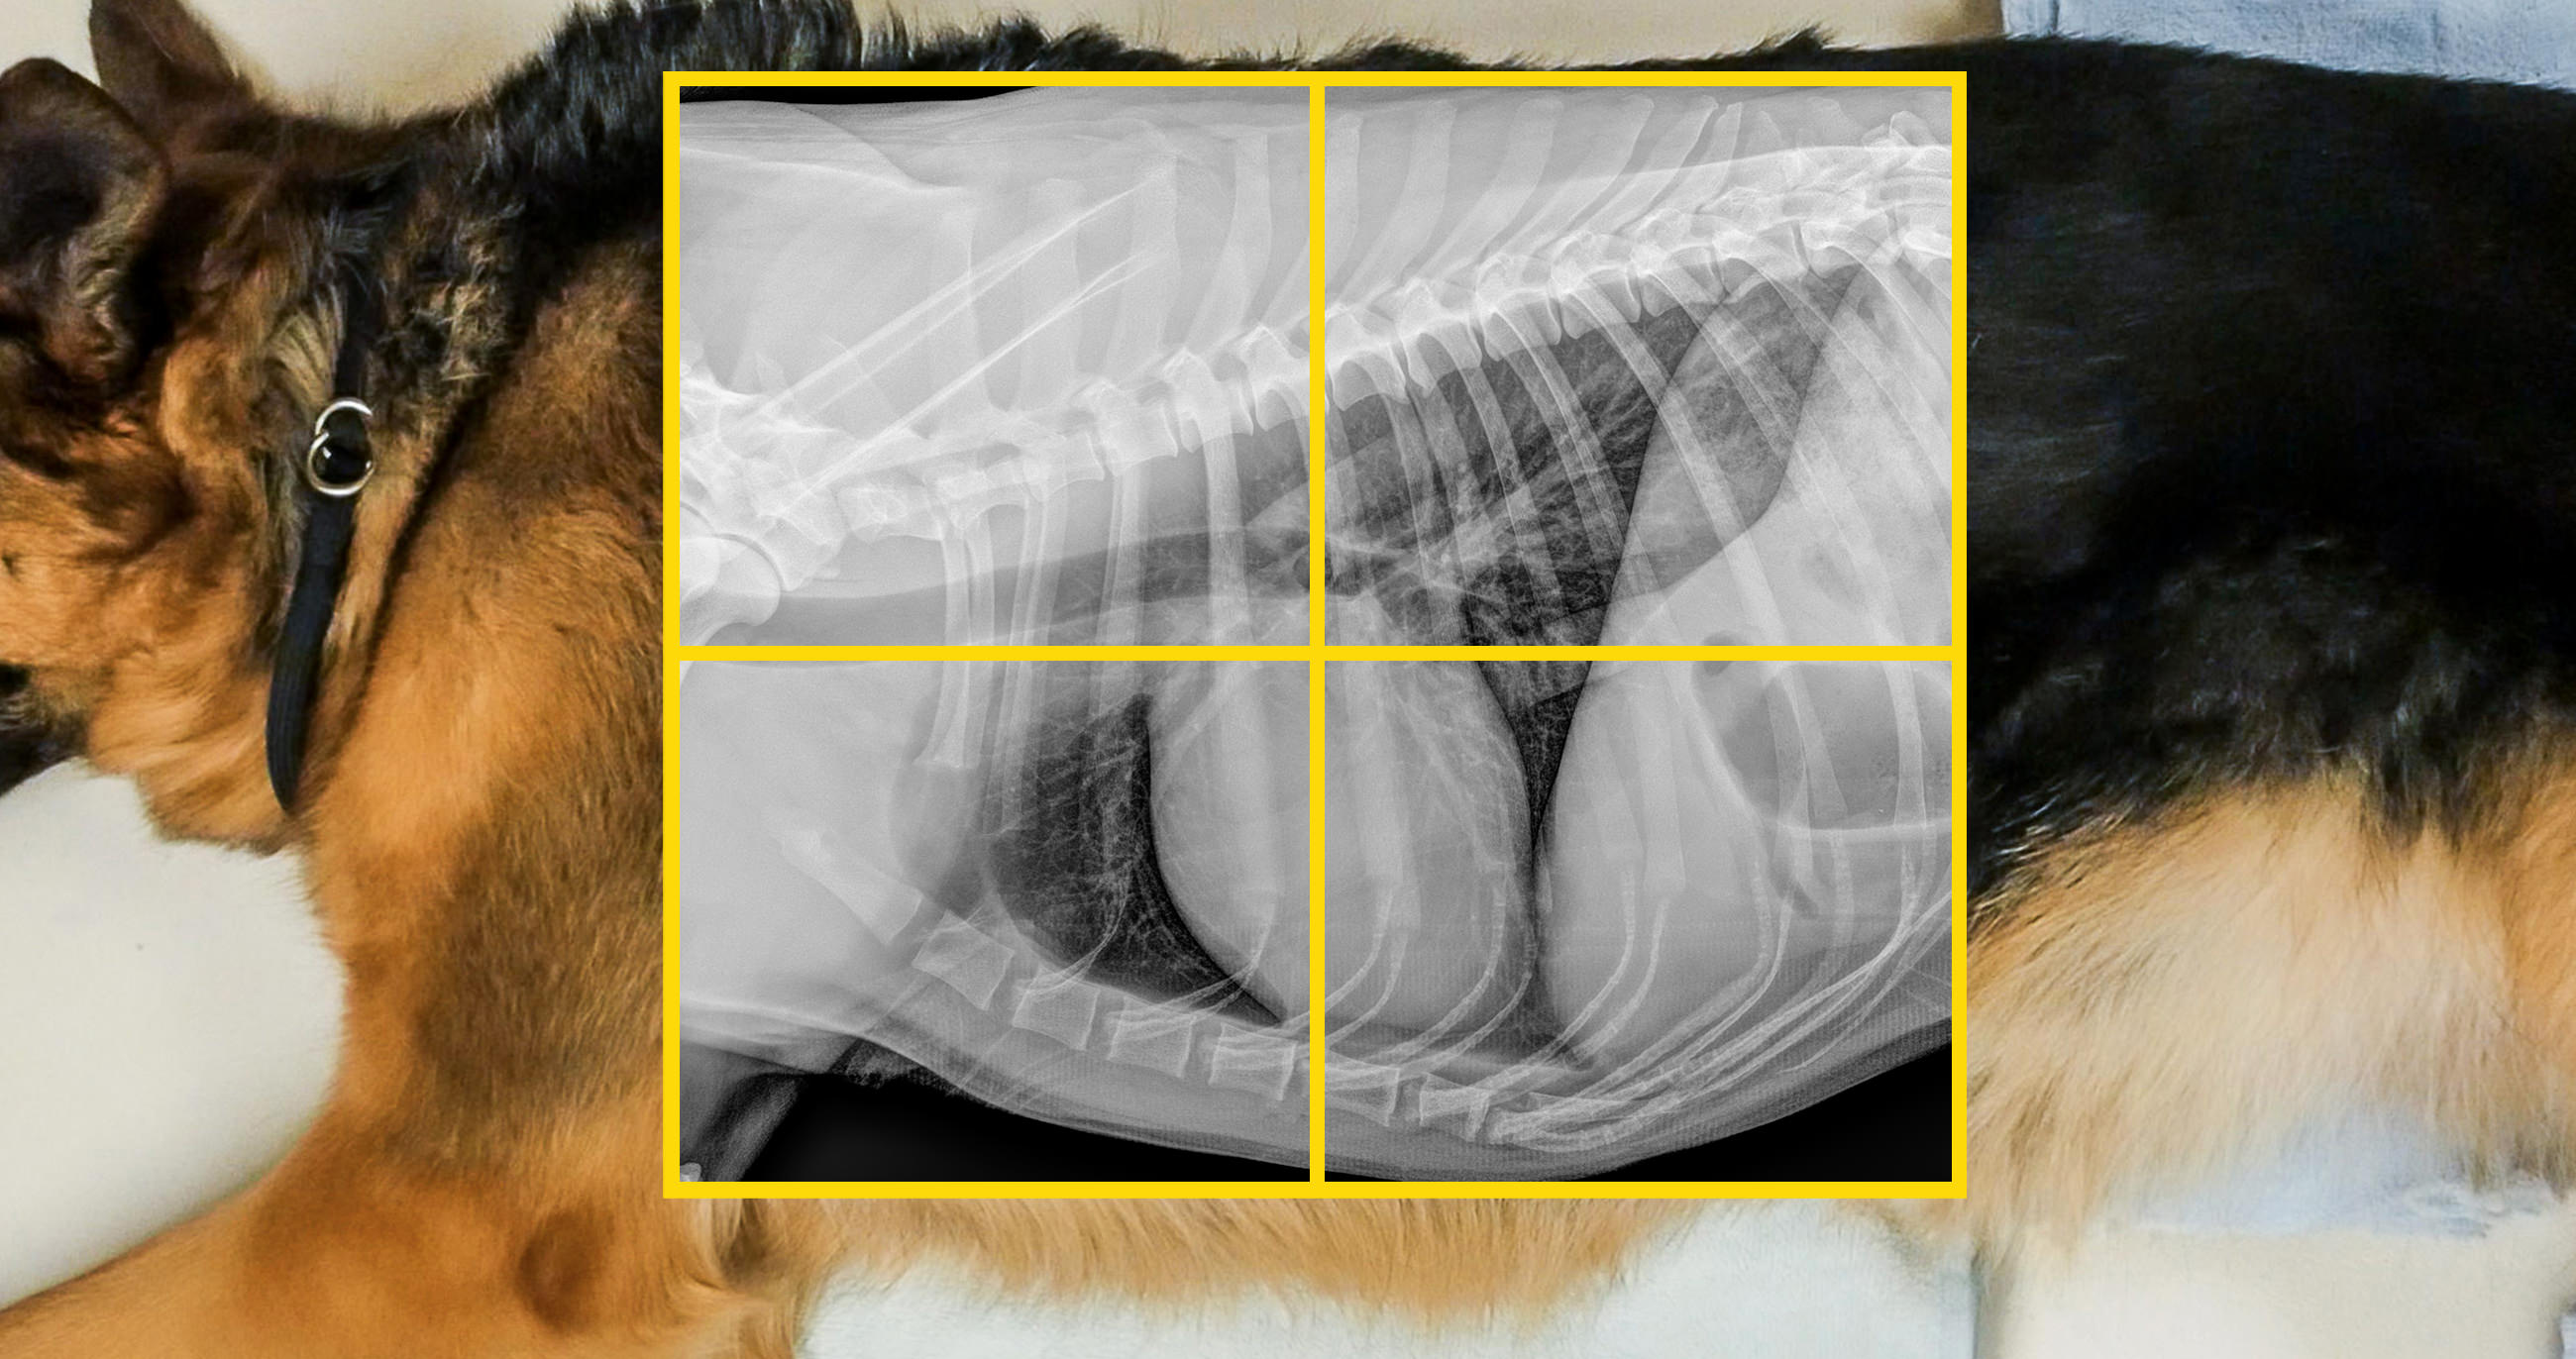

positionnement-thorax